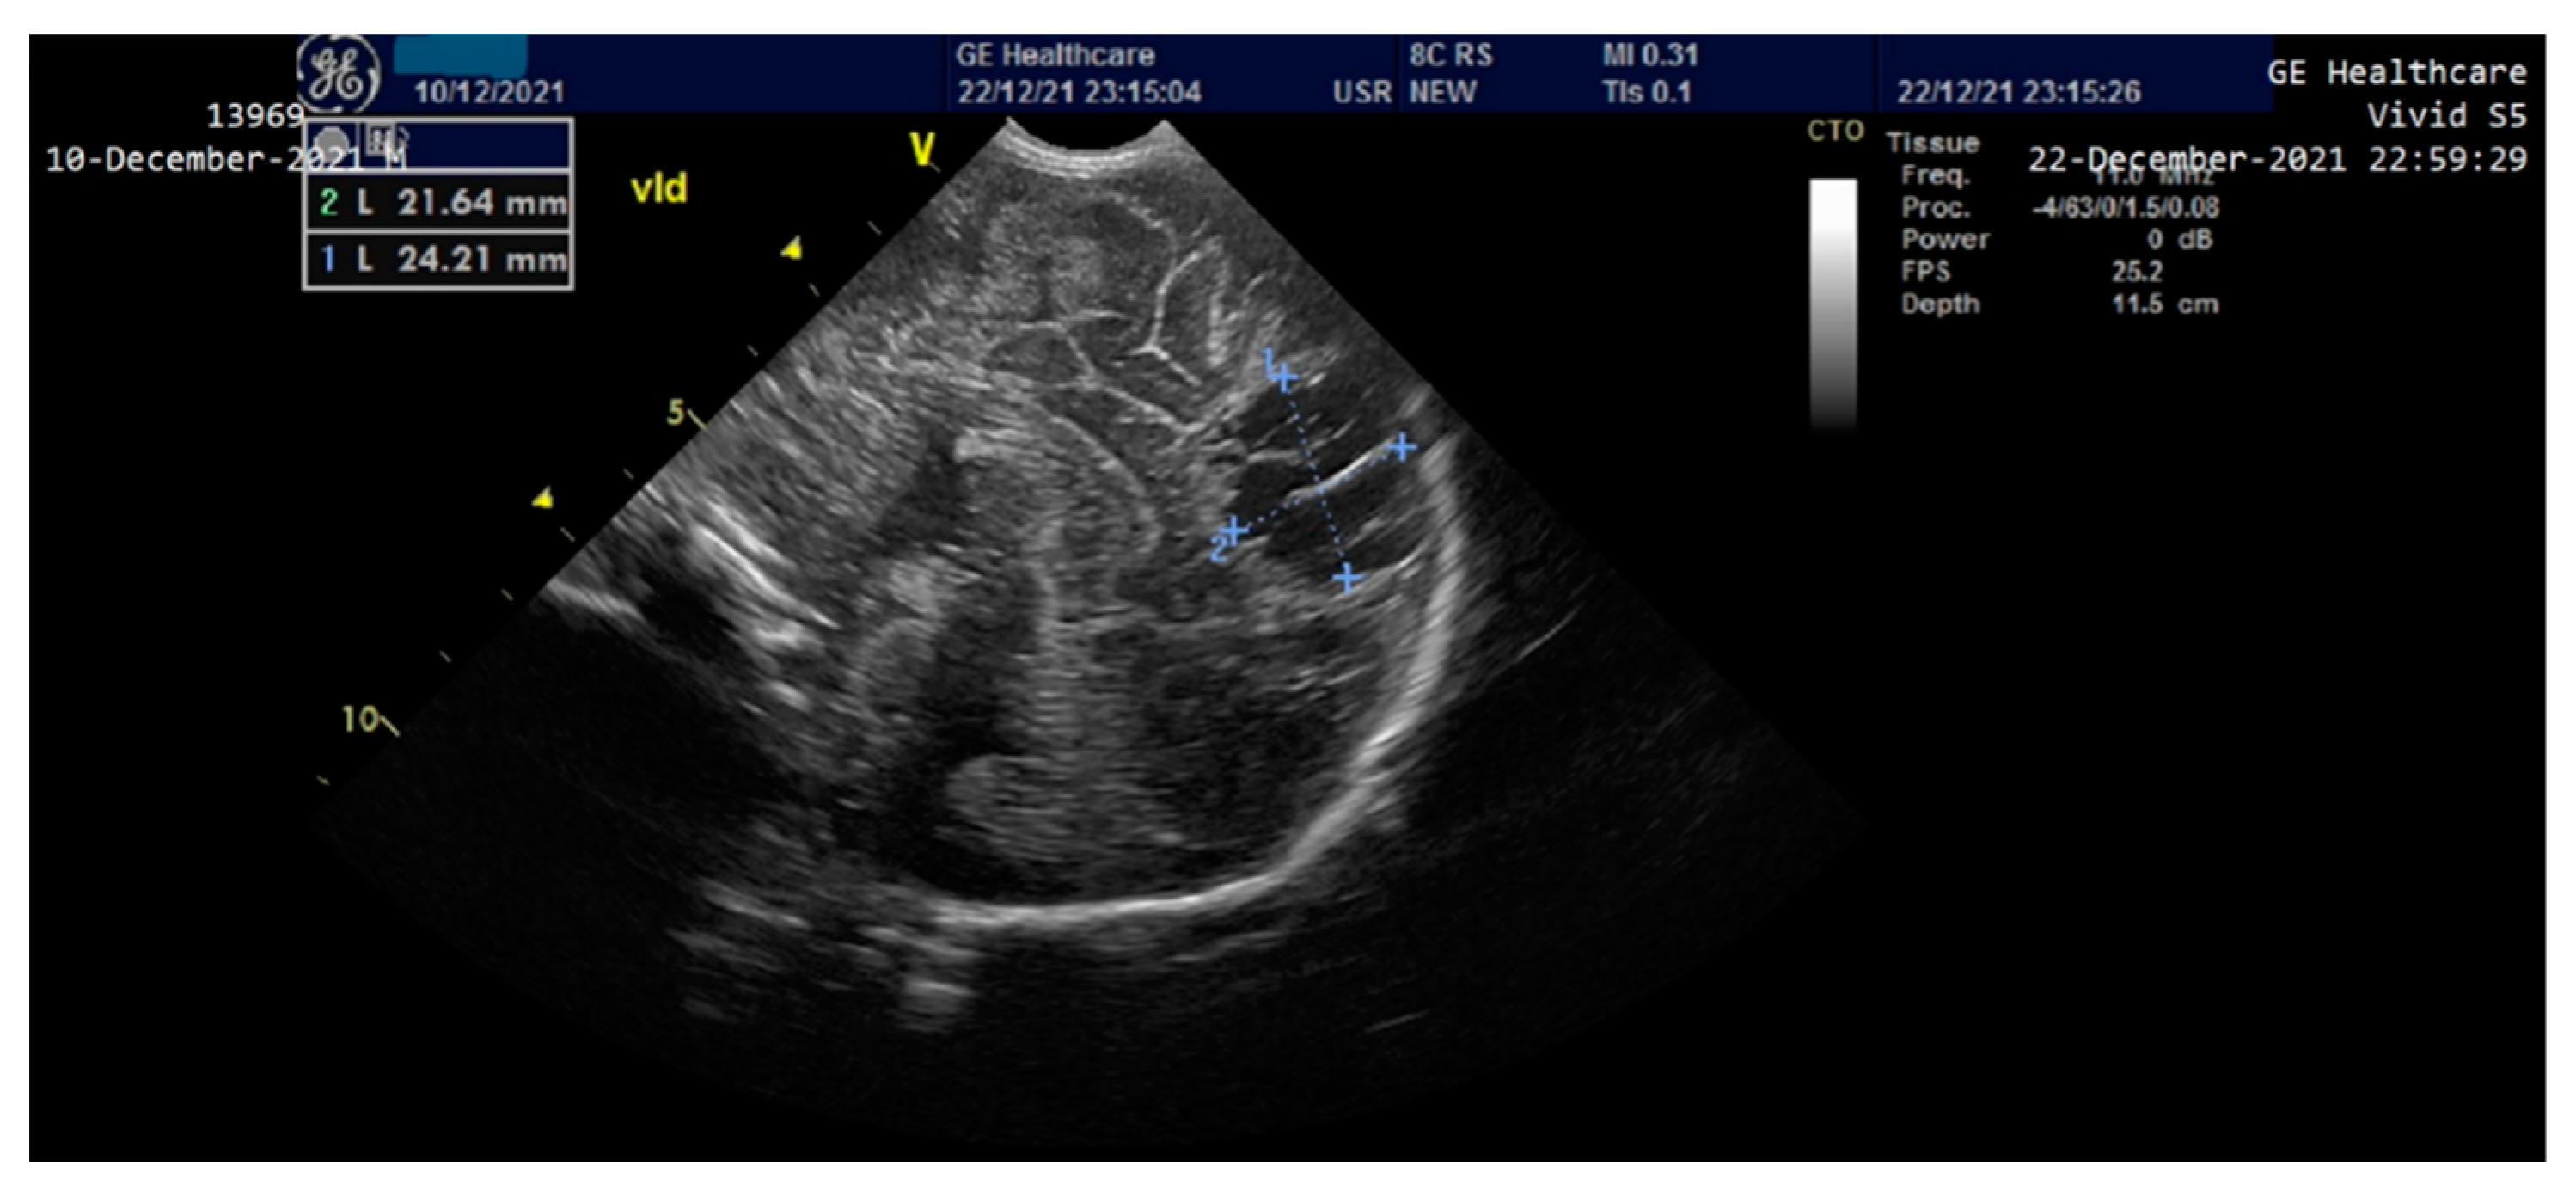

The newborn was admitted to the NICU with an extremely severe condition, pale skin, generalized edema with the appearance of hydrops, generalized purpura, ecchymosis of the cephalic extremity, parietooccipital cephalohematoma, abdomen with important wall edema and ascites fluid. Thoracoabdominal radiography and abdominal ultrasound showed the presence of ascites fluid and poor aeration of the colic frame (Figure 2).

Figure 2.

Thoraco-abdominal X-ray-poor aeration of the colic frame, ascites fluid.

The newborn exhibited hepatomegaly with the right lobe extending caudally. Enlarged hepatic vein and associated splenomegaly were observed on abdominal ultrasound. A cardiac ultrasound revealed mild pulmonary hypertension, mild sized patent ductus arteriosus with left to right shunt, patent foramen ovale with left to right shunt, representing mild cardiac involvement which responded accordingly to the inotrope and vasopressors agents.